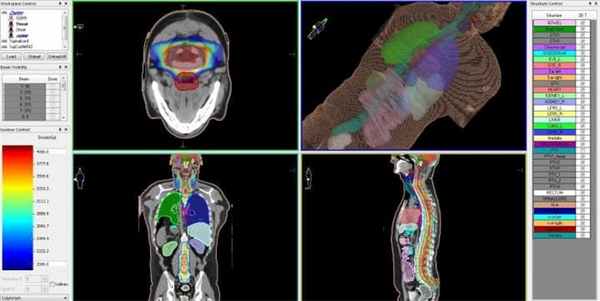

Лучевая терапия IMRT

Линейный ускоритель Elekta

Если объем новообразования достаточно большой, и не позволяет применить радиохирургический метод, лечение эпендимомы предусматривает удаление злокачественного очага хирургическим путем с последующим облучением на высокоточном линейным ускорителе с функцией IMRT.

Лучевое лечение эпендимомы головного мозга на линейном ускорителе с принципом IMRT во многом соответствует принципу радиохирургического лечения опухолей на КиберНоже. Точность лучевой терапии, также как и при радиохирургии, обеспечивает контролируемая доставка высокой дозы ионизирующего излучения точно в объем опухоли, пространственные контуры которой составлены компьютерной системой планирования.

Перед тем как приступить к лечению, пациент проходит комплексную КТ- и МРТ-диагностику, на основании результатов которой лучевым терапевтом совместно с медицинским физиком составляется цифровая компьютерная трехмерная модель расположения опухоли и здоровых тканей вокруг нее, которые не должны быть подвергнуты облучению.

Эпендимома головного мозга — план лечения на линейном ускорителе, с распределением доз облучения для различных типов биологических тканей

Принцип действия IMRT-лучевой терапии состоит в том, что для каждой зоны, в соответствии с виртуальной компьютерной моделью, задаются максимальные и минимальные дозы ионизирующего облучения. Это позволяет доставлять в границы опухоли и пути ее метастазирования максимально высокие дозы излучения, необходимые для разрушения раковых клеток, а в зону расположения критических структур головного мозга — нулевые.

После того, как план лечения утвержден, пациенту назначается первый сеанс (фракция) лучевой терапии. Лечение проходит амбулаторно и не требует анестезии. Во время сеанса лучевой терапии пациент удобно располагается на специальном столе, а подвижная часть линейного ускорителя последовательно занимает различные положения, подавая необходимую дозу ионизирующего излучения в опухолевый очаг. Конфигурация каждого пучка излучения, точно повторяющего форму опухоли, формируется многолепестковым коллиматором, который управляется системой согласно заданному плану и контролируется ответственным врачом.

Лучевая терапия IMRT проводится таким образом, что наиболее высокие дозы облучения, необходимые для гибели раковых клеток, доставляются только в границы опухоли, а здоровые ткани вокруг нее поддаются наименьшему влиянию облучения. При этом наиболее важные структуры организма (ствол мозга, аорта, слюнные железы и др.) во время лучевой терапии абсолютно защищены — для них еще на стадии планирования лечения задается зона нулевого воздействия, так называемая «холодная зона».

Лечение на линейном ускорителе, как правило, не требует никакой специальной подготовки пациента – во время фракций лучевой терапии пациент находится в сознании, а подвижная часть линейного ускорителя последовательно занимает указанные в плане лечения положения, в каждом из которых проводится излучение требуемого поля. Количество фракций зависит от множества индивидуальных факторов, поэтому длительность, состав терапии и стоимость лечения определяются для каждого пациента его лечащим врачом. После завершения каждого сеанса лучевого лечения, каждый из которых длится в среднем 30-40 минут, пациент может вернуться к обычному распорядку своего дня